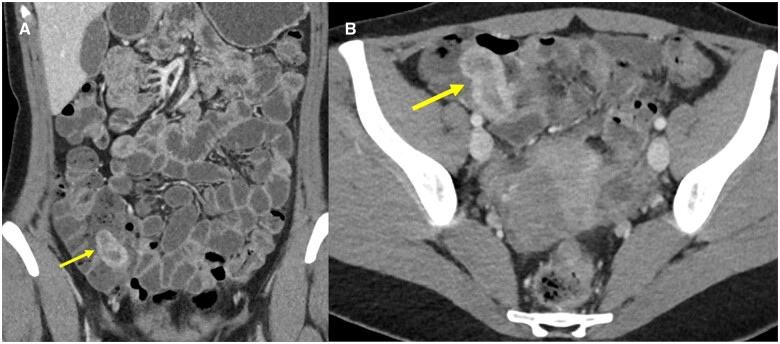

阑尾肠套叠是一种罕见疾病,其特征是部分或整个阑尾伸缩或内陷到盲肠或阑尾本身。由于其罕见性、非特异性症状以及医生缺乏认识,阑尾肠套叠的诊断具有挑战性。我们报告了一例年轻女性因子宫内膜异位症引起阑尾肠套叠并伴有反复腹痛的病例,该病例最初在 CT 扫描和腹腔镜检查中被漏诊,最终在 CT 肠造影检查中被确诊。

Appendiceal intussusception is a rare condition characterized by the telescoping or invagination of a portion or the entire appendix into the caecum or within the appendix itself. Diagnosing appendiceal intussusception can be challenging due to its rarity, non-specific symptoms, and lack of awareness among physicians. We present a case report of appendiceal intussusception caused by endometriosis presenting with recurrent abdominal pain in a young female that was initially missed on CT scan and laparoscopy and eventually diagnosed on CT enterography.